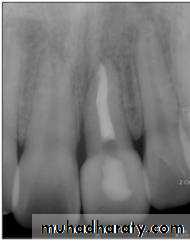

Internal resorption with perforation.

Vertical root fracture.